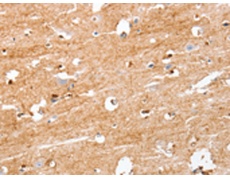

IHC positive control: |

Human brain |